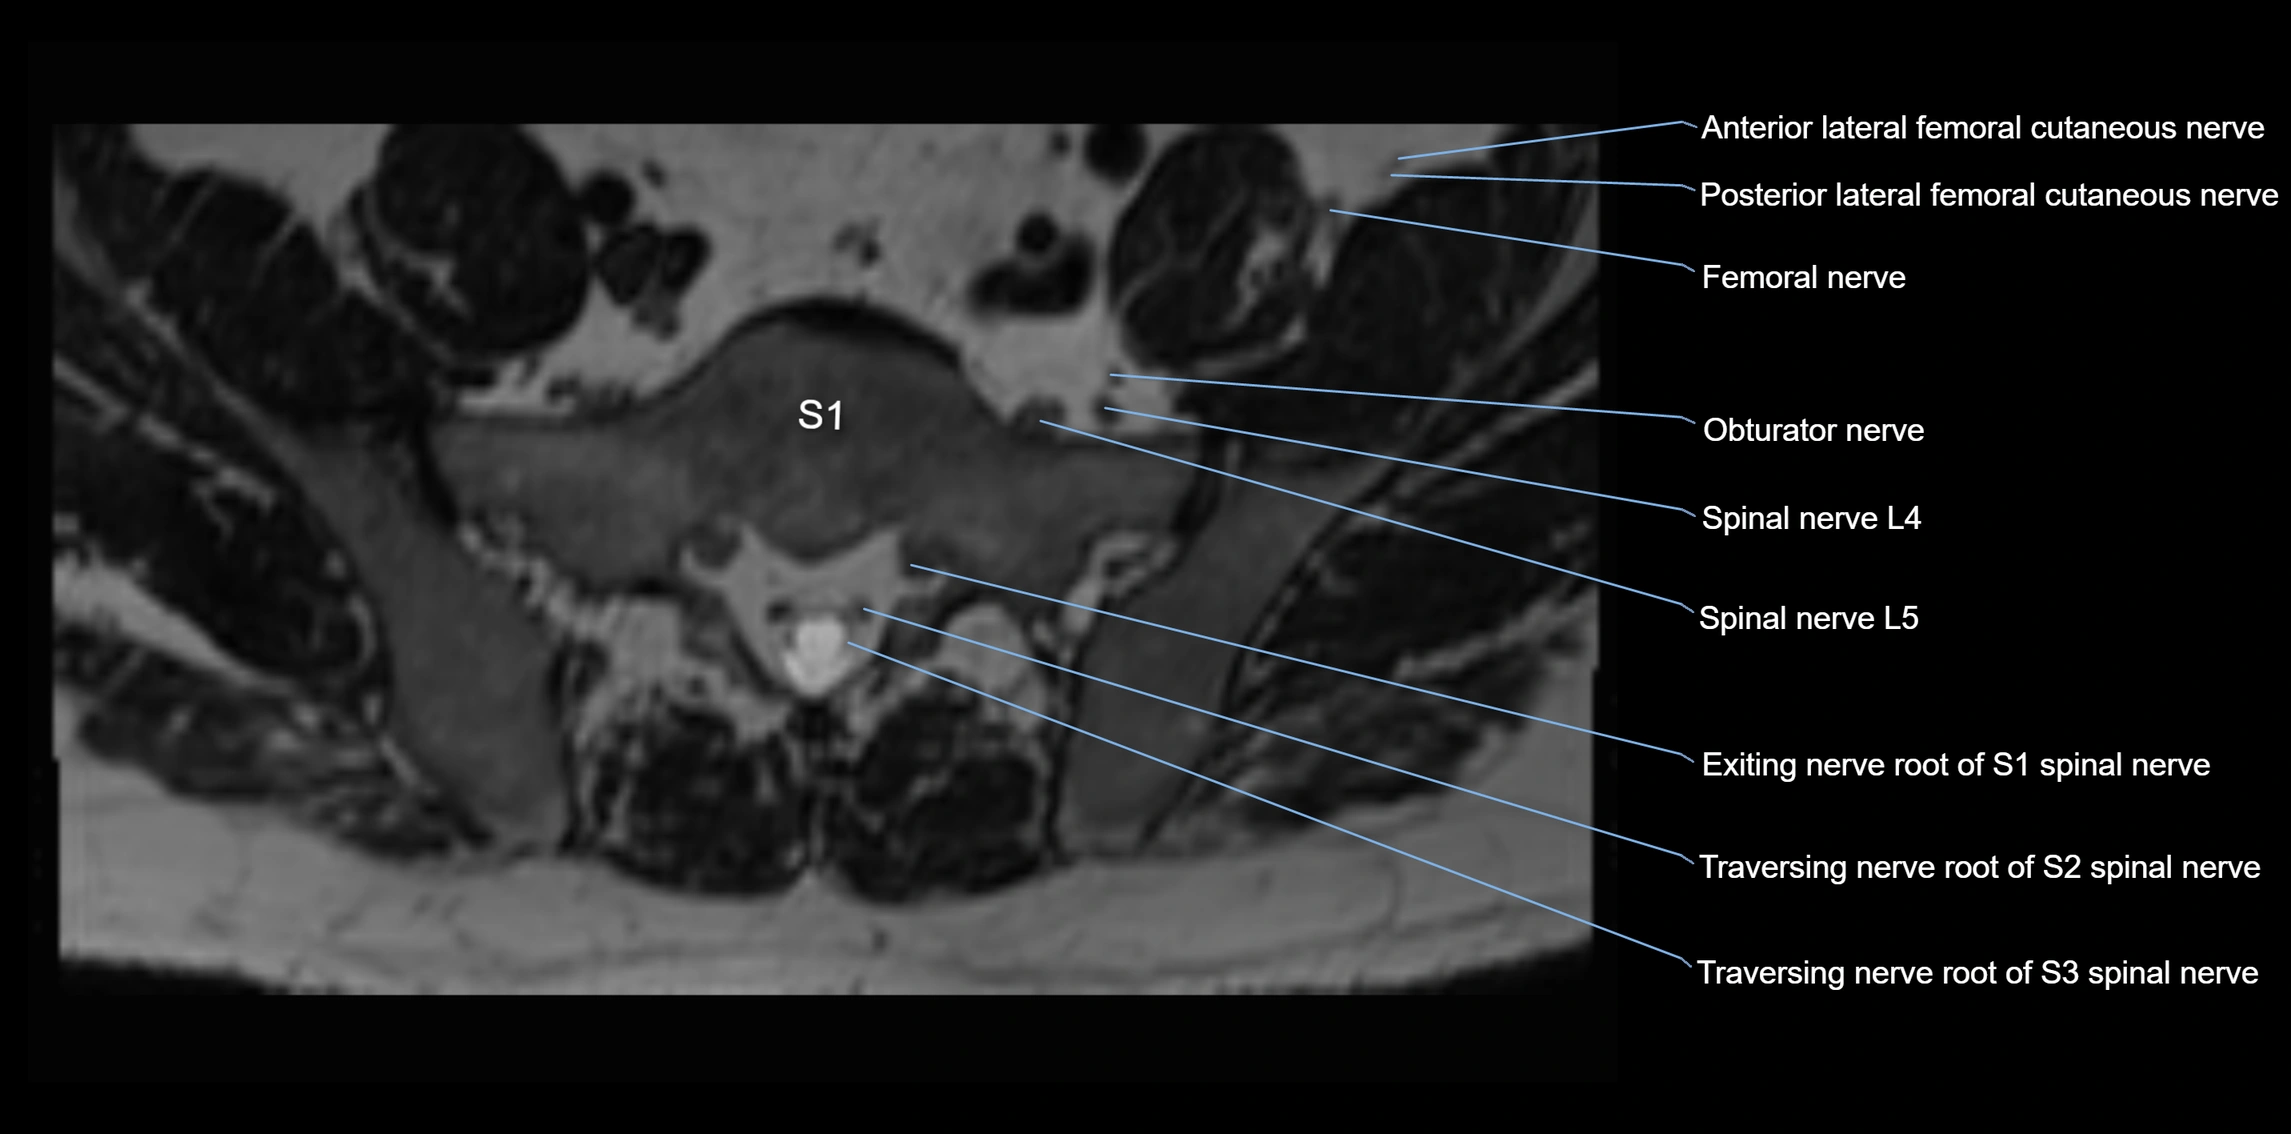

MRI image

image